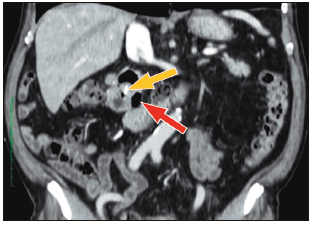

Con los hallazgos mencionados, se realizó el diagnóstico de colangitis grado II (sobre la base de los criterios diagnósticos y de severidad de las guías de Tokyo),6 y se inició tratamiento antibiótico. Posterior a las primeras 24 horas del diagnóstico, el paciente fue sometido a CPRE, en la que se identificaron tres divertículos duodenales periampulares. Debido a que la canulación fue difícil, tuvo que realizarse, durante el procedimiento, la técnica de rendez-vous (guiada por ecografía y fluoroscopía), utilizando el acceso transparietohepático para lograr el ingreso a la vía biliar. En la colangiografía, el conducto biliar se encontraba dilatado (10 mm) y no se evidenciaron imágenes por defecto de relleno. Se realizó una esfinterotomía mínima y se colocó una prótesis biliar plástica de 10 Fr x 7 cm para poder asegurar un adecuado drenaje de la vía biliar. El paciente evolucionó favorablemente. Al momento del alta no presentaba dolor abdominal, había normalizado los valores de leucocitos y PCR, y los valores de colestasis se encontraban en descenso. En los controles posteriores, el paciente presentó dolor abdominal esporádico en el CSD, pero el examen físico y los análisis de sangre no mostraron mayores alteraciones. El paciente contaba, además, con una tomografía abdominal con contraste, que no aportó información adicional a la evidenciada en la CPRM (Figuras 2 y 3).

Figura 2. Tomografía abdominal (corte coronal): divertículo duodenal periampular

(flecha roja) y prótesis biliar plástica en el conducto biliar común (flecha

amarilla).